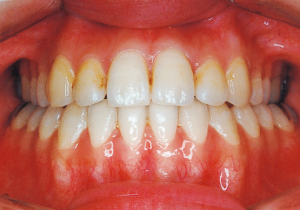

Age at Initial Visit: 8 years 1 month, Female / Protruding lower bite. Protruding lower jaw

Although there were many missing deciduous teeth, the number of permanent teeth was not problematic (4). The amount of negative overjet was significant (1). On cephalometric radiographs, the mandibular ramus was not relatively long, but the large gonial angle and the long mandibular body were noticeable, indicating an overall tendency of the mandible to project inferiorly and anteriorly. High lower facial height was also characteristic.

A potential predisposition to mandibular protrusion was clearly evident.